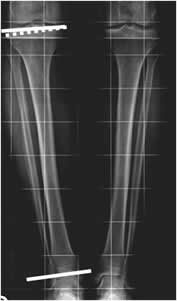

Fig 103. Longitud de extremidades.

A y B: Rx simple. Medición de las extremidades. En el fémur desde el borde superior de la cabeza femoral, hasta el borde inferior del cóndilo medial y en la pierna desde la eminencia intercondilea, hasta el borde inferior de la tibia.

Fig 104 A. Acortamiento.

Test de Farill. Acortamiento de la extremidad izquierda, a expensas del fémur.

Fig 104 B. Acortamiento.

Rx AP. Acortamiento de la extremidad izquierda, a expensas del fémur por fractura antigua y consolidada del tercio distal.

Fig 105. Acortamiento.

Rx AP. Acortamiento de la extremidad izquierda, sin encontrar lesiones focales y secundario a disminución en la longitud de la tibia.